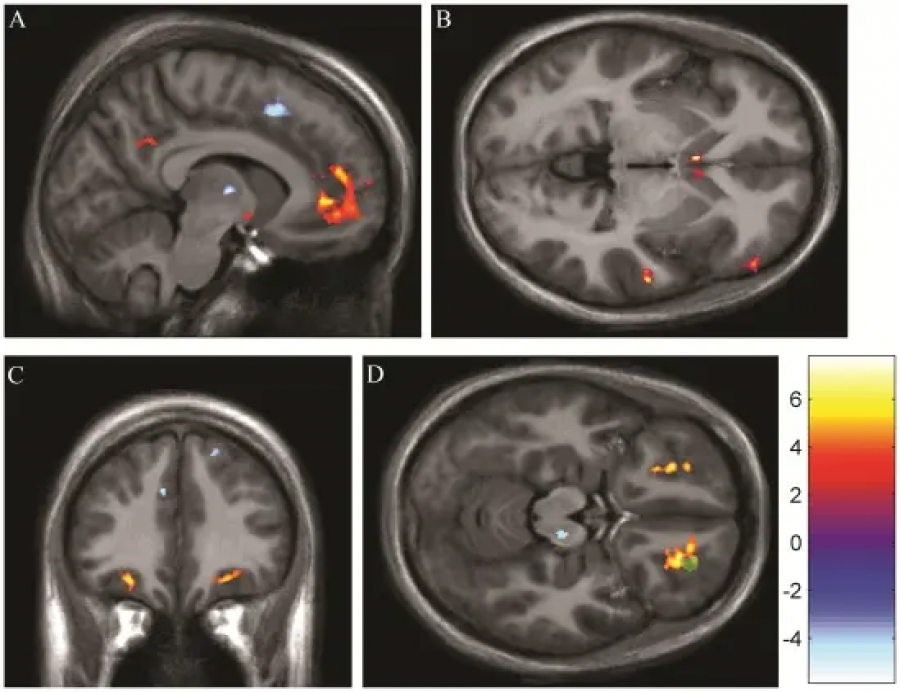

Stanford Üniversitesi Tıp Fakültesi tarafından, sevginin acı hissini azaltıcı ve ağrı kesici görevi yapıp yapmadığını araştırmak için bir deney yapılmıştır. Bu deneyde kadın ve erkeklerden oluşan katılımcıların ellerine sıcak test çubuğuyla hafif dozda ağrı verilir ve bu esnada içinde sevdiği insanların da bulunduğu bazı fotoğraflar gösterilir. Aynı zamanda katılımcıların beyinleri fonksiyonel bir manyetik rezonans görüntüleme makinesi ile taranır. Her testin sonunda öğrencilerden ne kadar acı hissettiklerini derecelendirmeleri istenir. Deneyin sonunda araştırmacılar; beyin taramalarını incelerken, katılımcıların sevdiği kişinin fotoğrafını gördüğü anda beyinlerinin ağrıyı azaltan bölgelerinde aktifliğin arttığını gözlemlemiştir. Bu durum sevilen kişinin bir fotoğrafıyla tetiklenen duyguların güçlü bir ağrı kesici etkisi olabileceğinin işaretidir.